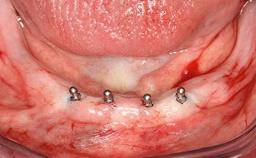

# of Implants 2

Type of Implants One-Piece

Attachment One-Piece

Defining Characteristics Fully edentulous lower jaw to be rehabilitated with two or more implants

Modality 2 interforaminal implants